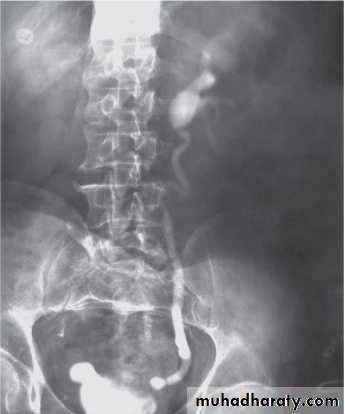

Grading of VUR

The degree of reflux is graded I–V.Grading is based on the appearance of contrast agent in the collecting system during voiding cystourethrography (VCUG(.

The VCUG:

the definitive examination

to diagnose and grade reflux and establish reversible causes

must include a voiding phase:

in some cases, reflux may be seen only during the elevated intravesical pressures associated with micturition.

in visualizing the urethra, may allow the diagnosis of outflow obstruction to be made (e.g., posterior urethral valves).

DMSA scan to detect and monitor associated renal cortical scarring.

The intravenous urography (IVU) findings are usually normal in lower grades of reflux.